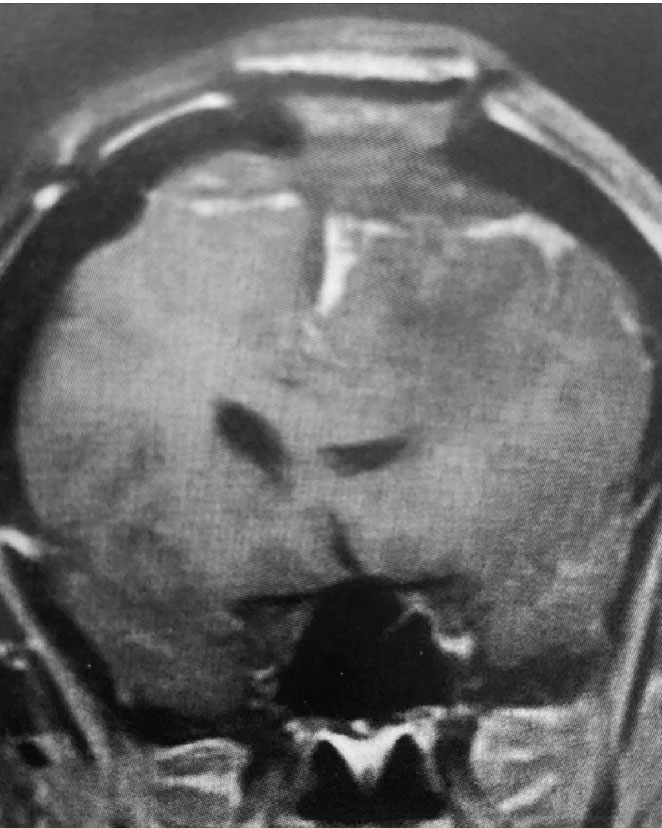

Fig 1. B) Pre-operative, sagittal post-contrast MRI.

This is a 55 year old right-handed woman who was having progressive balance problems. MRI with and without contrast demonstrated a 7 cm partly cystic meningioma involving the left frontal convexity and falx, and encasing the superior sagittal sinus. There was also tumor involvement of part of the convexity skull.

Convexity and Falx Meningiomas: While meningiomas can involve either the convexity or the falx alone, it is possible for such tumors to involve both structures. In this case, vascular supply to the tumor can originate from both dural sources. When meningiomas involve the convexity dura, the dura is often excised and replaced with a duraplasty (an artificial dural replacement). When tumors involve the falx, the falx itself is usually not removed in entirety.

Meningiomas that compress the motor strip: This meningioma was clearly compressing the left motor strip significantly, likely explaining the patient’s balance problems. That having been said, these tumors often have very distinct borders with the normal brain, and can be removed without harming the underlying motor strip.